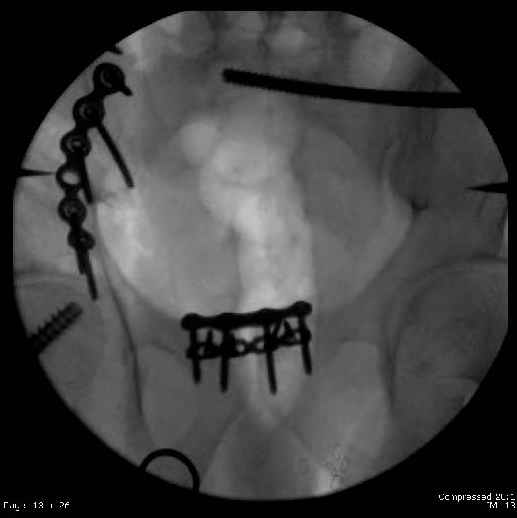

Here are the postop fluoros.

Fluoroed L SI joint and it seemed stable, but wide. So, applied c-clamp to try to squeeze down L SI joint (and note, on the last slide attached, that it's still wide), and got it closer. Single perc Iliosacral screw 40mm thread.

Applied second plate anteriorly on symphysis as I wasn't confident L SI was as stable as it could be and wanted to protect it better.